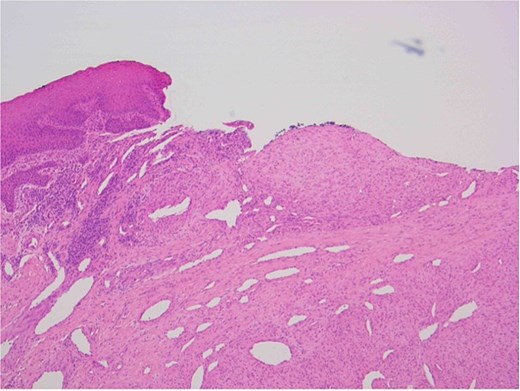

The patient underwent a biopsy of the lesion. Histopathological analysis revealed spindle cell proliferation arranged in a fascicular growth pattern, dilated hemangiopericytoma-like vessels, and a central myeloid nodule. Immunohistochemical staining was positive for smooth muscle actin (SMA), with no evidence of cellular atypia (Figs 5–7).

Oral squamous mucosa with underlying bland spindle cell proliferation showing fascicular growth and dilated haemangiopericytoma-like vessels and a myoid nodule centrally.

Ulcerated area with underlying bland spindle cell proliferation showing fascicular growth impression of cellularity involving vascular wall – haemangiopericytoma-like architecture (central).

Histologically, myofibromas show characteristic biphasic pattern with central zone of rounded cells and the peripheral zone of spindle cells [11, 12]. Immunohistochemically, myofibromas are SMA and vimentin positive, and S100 protein and desmin negative, aiding in differentiation from other spindle cell neoplasms [11, 12]. In our case, ameloblastoma was an important differential due to overlapping location and radiographic but aggressive with metastatic potential and high recurrence rates [5]. Thus, immunohistochemical staining is essential for accurate diagnosis [11].